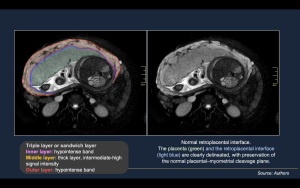

Normal MRI Findings

- Placenta (Figure 6-8).

- Homogeneous placental signal intensity on T2-weighted images

- Smooth placental contour

- Well-defined placental margins

- Absence of focal bulging or lobulation

- Normal placental thickness for gestational age

- Uteroplacental Interface and Myometrium (Figure 9-10).

- Continuous, hypointense retroplacental line on T2-weighted images

- Preserved decidua basalis and normal placental–myometrial interface

- Uniform myometrial thickness beneath the placenta

- Clear cleavage plane between placenta and myometrium